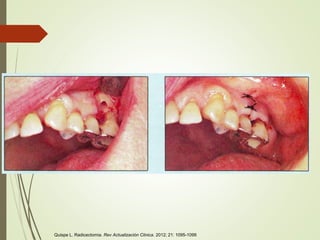

Quispe L. Radicectomia. Rev Actualización Clinica. 2012; 21: 1095-1099

Tecnica quirurgica

Rehabilitación protésica

Sellar remanente

Raspaje y alisado

Exodoncia

Sección radicular

Colgajo

Pulpectomía